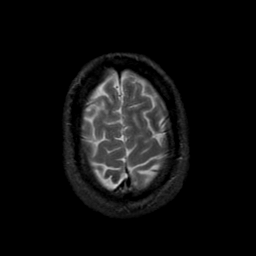

MR Study #23, January 26, 1992 -- Slice #43

[Home][Help][Clinical][Tour 1][Tour 2] Slice 43